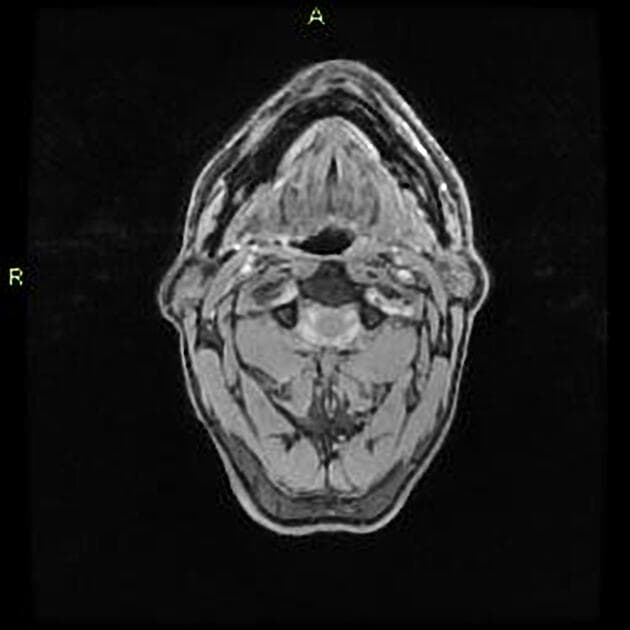

Axial T1

MRI•Axial T1•1 / 18

- Cộng hưởng từ (MRI) phát hiện một khối trong trục (intra-axial) lớn, tín hiệu không đồng nhất (heterogeneous signal) ở vùng thùy đỉnh - thái dương trái.

- Khối này gây hiệu ứng chiếm thể tích đáng kể, dẫn đến lệch đường giữa (midline shift), chèn ép sừng chẩm của não thất bên trái (left lateral ventricle occipital horn) và được bao quanh bởi phù vận mạch (vasogenic edema).

U nguyên bào thần kinh đệm IDH dạng hoang dại (WHO độ IV) là khối u ác tính nguyên phát phổ biến và nguy hiểm nhất ở não người lớn. Bệnh thường khởi phát nhanh với các triệu chứng như động kinh, suy giảm thần kinh hoặc liệt nửa người. Trên cộng hưởng từ, khối u hiện diện như một khối trong trục lớn, tín hiệu không đồng nhất, tăng quang dạng vòng không đều, hoại tử trung tâm và phù vận mạch lan rộng xung quanh. Hạn chế khuếch tán cho thấy mật độ tế bào cao. Lệch đường giữa và chèn ép não thất phản ánh hiệu ứng chiếm thể tích rõ rệt. Chẩn đoán xác định cần sinh thiết mô và phân tích phân tử: tế bào khối u dương tính với các dấu ấn thần kinh đệm (GFAP, Olig2), và xét nghiệm IDH1 âm tính trong dạng hoang dại. Khác với các u thần kinh đệm có đột biến IDH, ung thư dạng hoang dại thường gặp ở người lớn tuổi hơn và tiên lượng xấu hơn nhiều. Các chẩn đoán phân biệt bao gồm u di căn, ung thư hạch và u sao bào ác tính, nhưng hình ảnh học và miễn dịch mô hóa học giúp phân biệt rõ ràng.